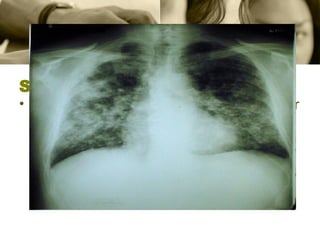

Silicosis La  silicosis  consiste en la  fibrosis  nodular de los  pulmones  y la dificultad para respirar causadas por la inhalación prolongada de compuestos químicos que contienen  sílice  cristalina.